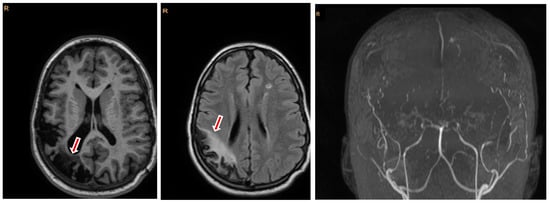

Figure 1

Background: Tuberculous meningitis (TBM) is the most severe manifestation of tuberculosis in children, with high mortality rates and long-term neurological sequelae. Early diagnosis is challenging due to its nonspecific symptoms and insidious onset. Case Presentation: An 8-year-old previously healthy male, fully vaccinated, presented with a two-week history of fever, headache, vomiting, and abdominal pain. Cerebrospinal fluid (CSF) analysis revealed lymphocytic pleocytosis, elevated protein, and low glucose levels, while multiplex polymerase chain reaction (PCR) testing for bacteria and viruses yielded negative results. Brain computed tomography (CT) revealed mild ventricular dilation and pansinusitis. Empirical antibacterial and antiviral therapy were initiated; however, the patient subsequently experienced neurological deterioration, including cranial nerve deficits and hemiparesis. Brain magnetic resonance imaging (MRI) demonstrated acute infarctions of the basal ganglia, raising suspicion for TBM. Repeated CSF sampling and Xpert MTB/RIF assay confirmed infection with Mycobacterium tuberculosis. Anti-tuberculosis treatment was initiated in combination with adjunctive corticosteroids, anticonvulsant and anticoagulant therapies, and supportive care, including neurosurgical intervention for hydrocephalus. After 16 months of treatment, the patient showed clinical improvement but sustained left-sided hemiparesis, visual impairment, and cognitive deficits. Conclusions: This case highlights the diagnostic challenges of pediatric TBM in immunocompetent and Bacillus Calmette–Guérin (BCG)-vaccinated children, particularly in the presence of initially negative microbiological findings. It emphasizes the importance of maintaining a high index of clinical suspicion and the crucial supportive role of neuroimaging findings, as well as the earlier initiation of empirical TB therapy especially when epidemiological plausibility exists. Early recognition and intervention remain critical to reducing morbidity and mortality associated with this devastating disease. Full article